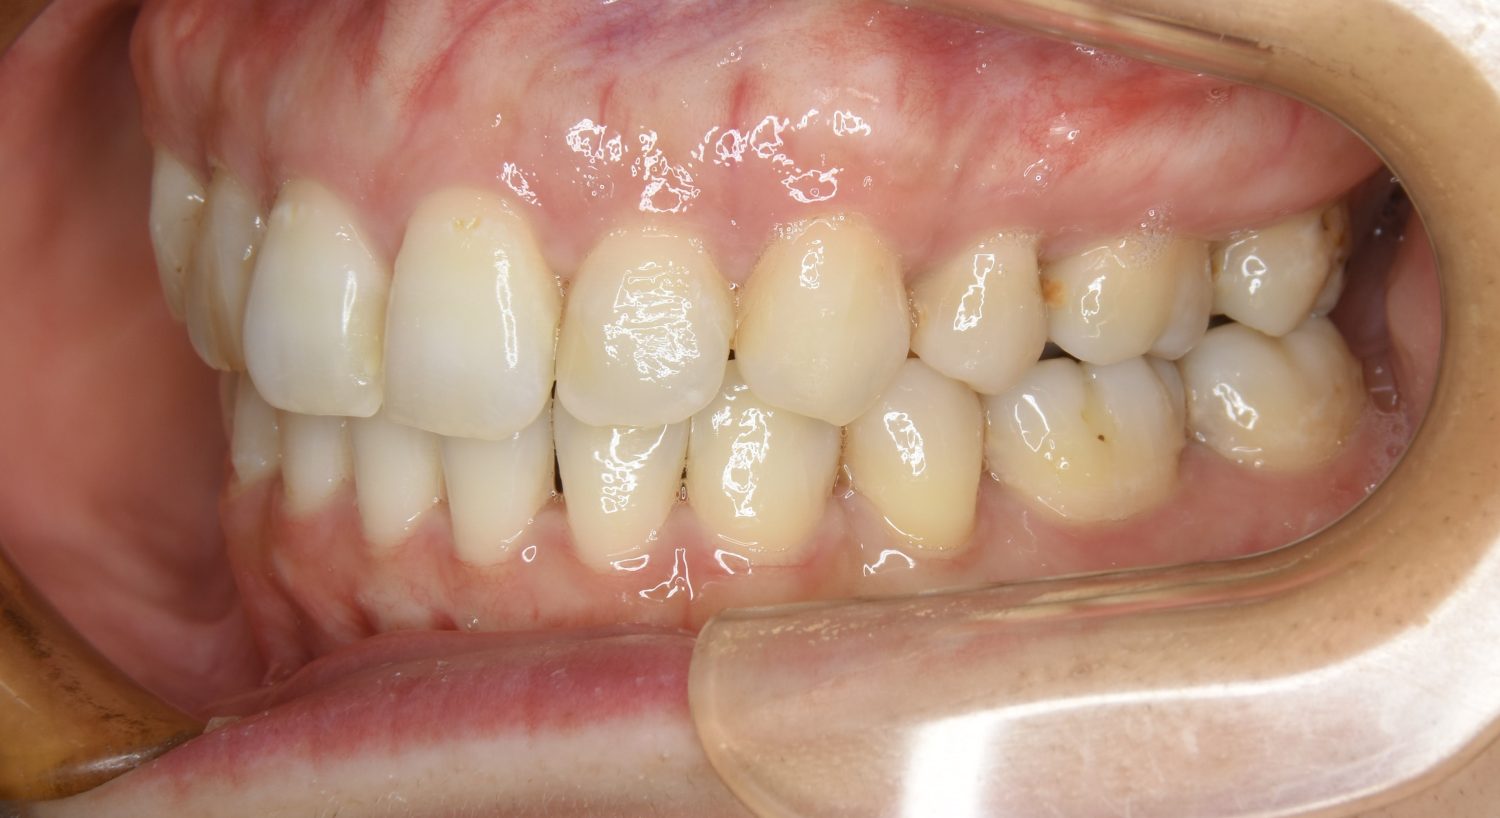

叢生の症例紹介①

Before

After

主訴

前歯のガタガタが気になる。

治療内容

上顎左側第一小臼歯を抜歯し、アライナー(インビザライン)にて治療を行いました。

治療費

1,150,000 円(税込)

治療期間

23ヶ月

通院回数

13回

想定されたリスク

※歯根吸収、歯肉退縮、歯髄壊死、顎関節症状

※アライナー(インビザライン)は日本の薬機法未承認の矯正装置であり、医薬品副作用被害救済制度の対象外となる場合があります。

丸山和宏先生

ピーススマイル矯正歯科

左上の側切歯が完全に内側に入り込んでいる状態でした。左上の第一小臼歯のみ抜歯を行い治療を行うことで機能面および審美面を改善しました。